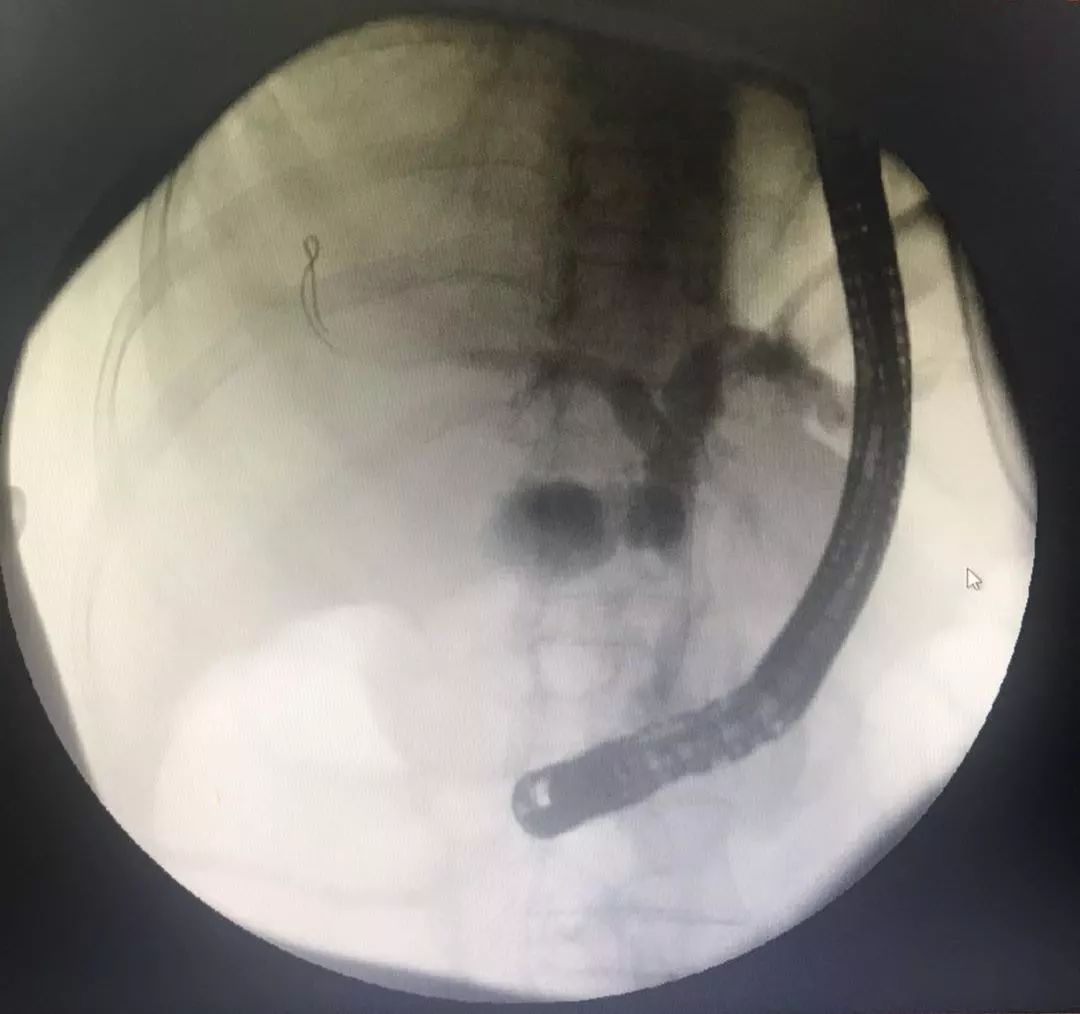

造影示:胆总管上段梗阻

沿11点方向切开十二指肠乳头约0.3 cm,见墨绿色胆汁涌出。保留导丝,经导丝置入一8mm×60 mm无覆膜胆道金属支架,支架下端位于乳头开口下方1.0 cm处,支架上端过狭窄段约2cm,见有大量脓性胆汁涌出。内镜操作顺利,麻醉满意,未出现出血,穿孔、胰腺炎等并发症。

造影示:支架位置良好